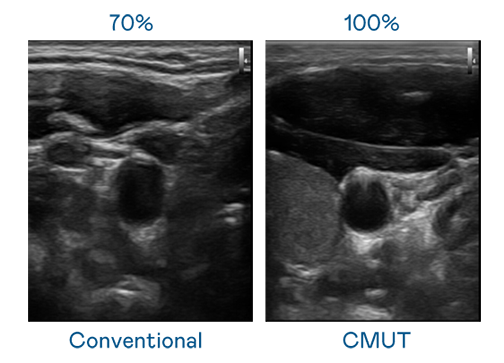

CMUT 技術是一種用電容式微機電元件來產生超音波訊號的技術。與傳統 PZT 壓電式技術相比,CMUT 頻寬增加 30%,更寬頻的超音波訊號讓影像解析度大幅提升,是實現高影像品質醫療超音波掃描、促進精準醫療發展的關鍵技術。

超音波影像的解析度高低,首先取決於探頭能發出的訊號頻寬。六合联盟 CMUT 可提供高清晰的超音波訊號,提供高頻寬、高靈敏度、影像紋理細節更高的超音波影像,協助醫護人員縮短影像判讀時間及利用精準的醫療影像進行診斷。